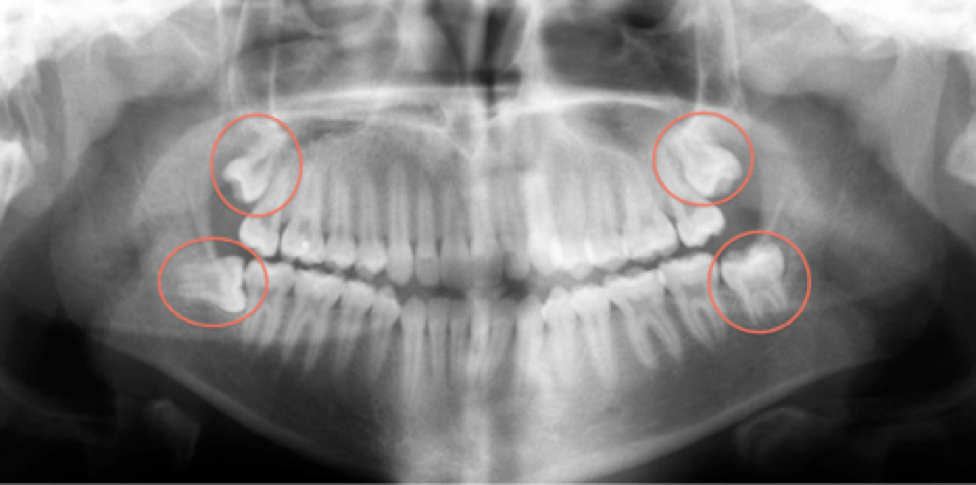

Complex conditions like impacted wisdom teeth, jaw misalignments, and facial trauma require the expertise of a specialized surgeon.

For instance, impacted wisdom teeth can cause significant pain, infection, and damage to adjacent teeth.

Early intervention is particularly important in wisdom teeth removal to prevent complications and ensure better outcomes.

Patients have shared positive experiences with having their wisdom teeth removed at Mahogany Oral Surgery, highlighting the comfort provided by the staff and the professionalism of the oral surgeons. For example, treating impacted wisdom teeth early can prevent infection and alignment issues. Addressing jaw misalignments early can reduce the risk of chronic pain and improve function. Early intervention in facial trauma can enhance healing and minimize scarring.